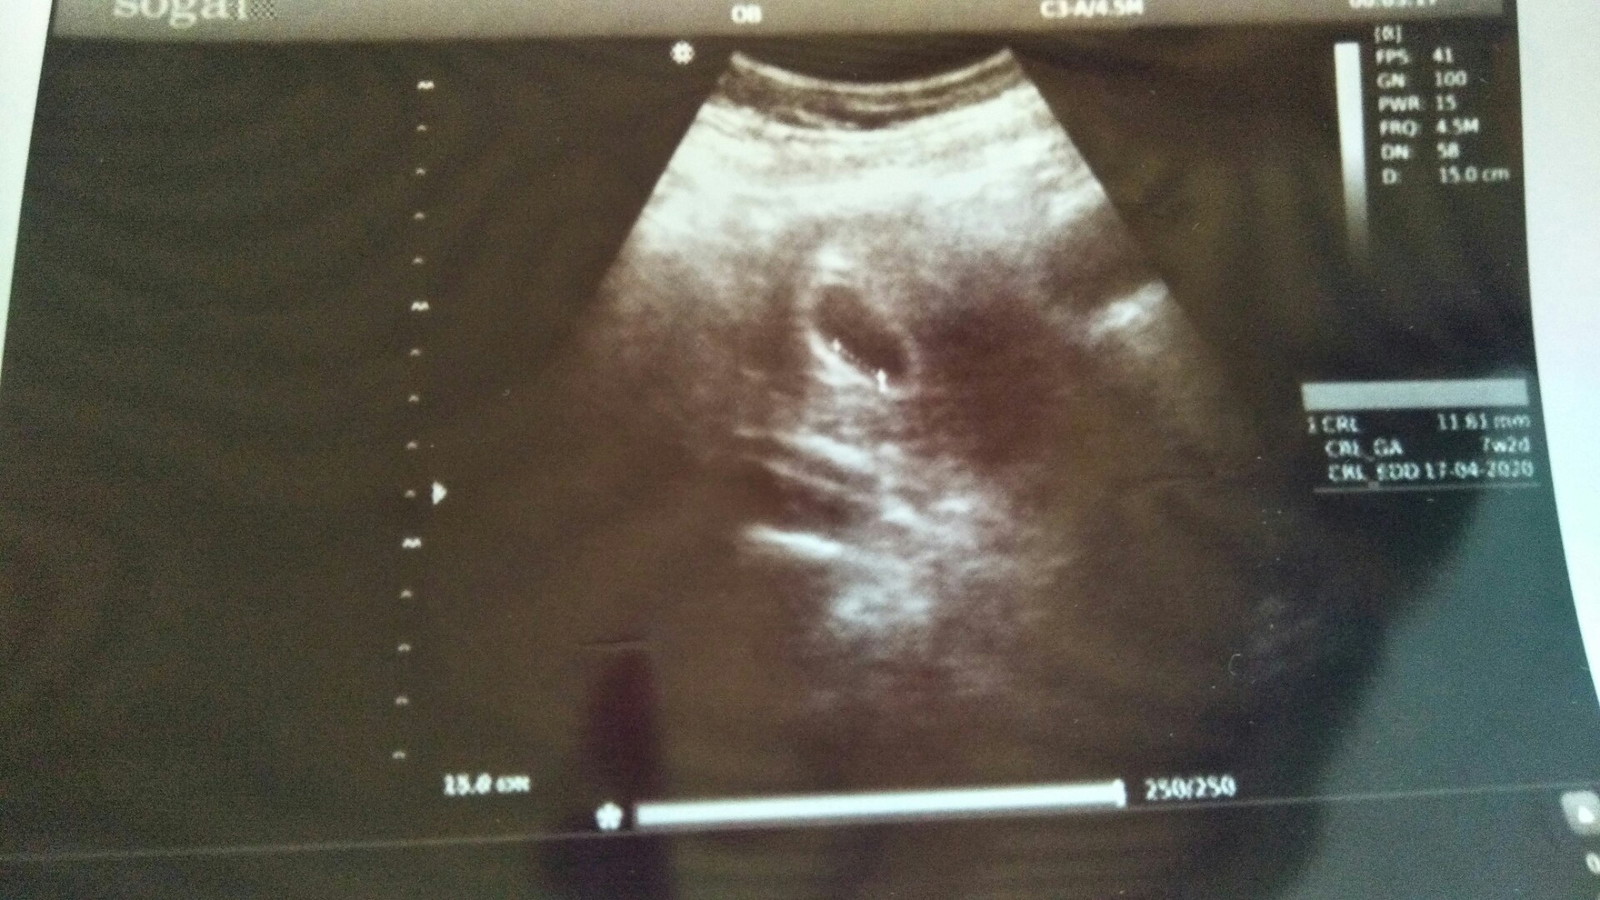

Bun,usia 6w gambar usg nya kygini normal ga sih Bun?? Tadi dokternya bilang, ga berkembang masa?? Disuruh balik lagi seminggu selanjutnya untuk di usg lagi

Saya 7w2d juga msh kantong kok bun π£